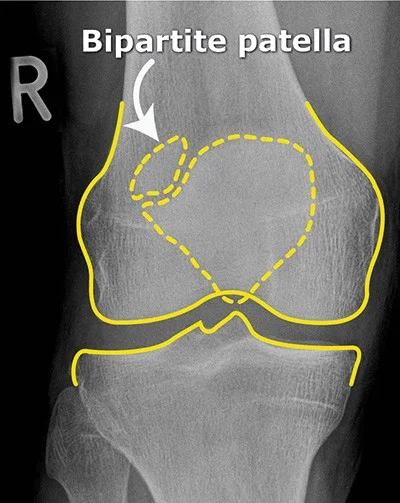

Bipartite Patella - Normal Variant

- No localized tenderness

- Superolateral

- Line not that of a fresh fracture